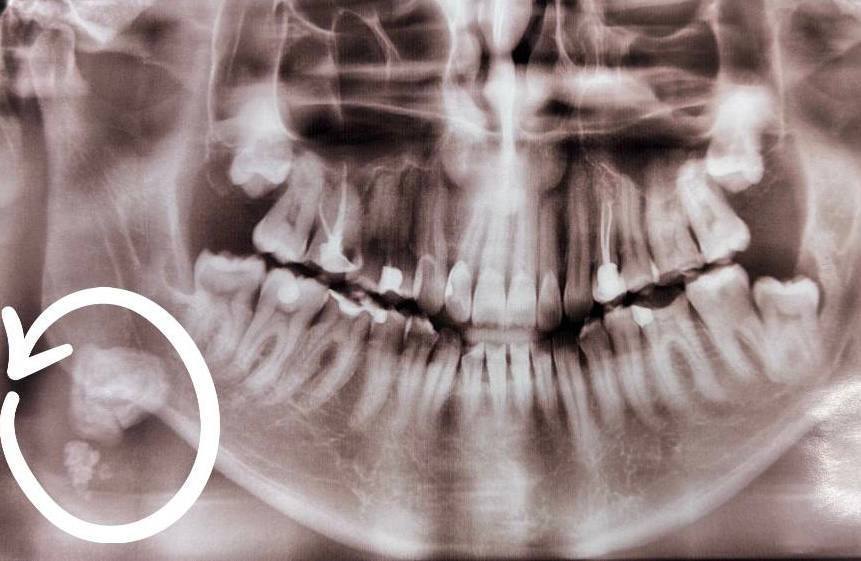

Пациент пришёл на профилактический осмотр. Во время обследования выяснилось, что в протоке поднижнечелюстной слюнной железы имеются плотные образования.

Хирург-стоматолог удалил крупный камень около 20 мм в диаметре.

Другие фрагменты вышли самостоятельно спустя месяц.